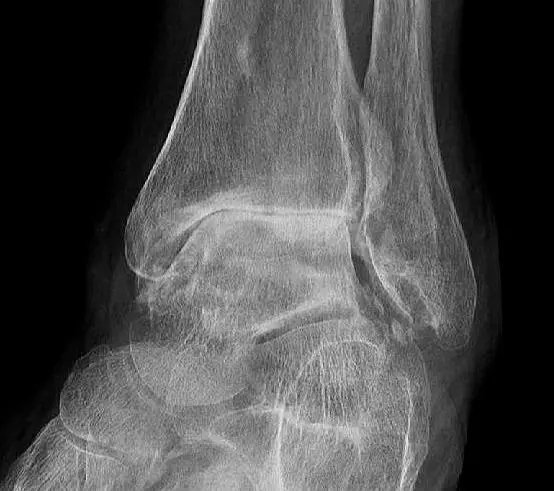

足与踝关节的骨关节炎也会导致肿胀

骨关节炎的病理基础是关节软骨的磨损,随着病情的加重,软骨磨损会越来越重,关节的间隙就会越来越狭窄,那么我们的身体为了让关节更加的稳定,就会慢慢的形成骨赘,也就是我们都耳熟能详的骨质增生、骨刺,来帮助增加关节的面积,增加关节的稳定性,但如果这骨赘形成的太多,就有可能影响到周边的软组织以及血供。

发生在足踝部的骨质增生,如果病情比较严重的话,因为这些部位周边的软组织本来就不是特别的厚,往往都是比较细的部位,增生的如果比较明显,压迫到周边的软组织,对血供的影响也就比较大,所以非常容易出现肿胀,而这种肿胀往往是在劳累以后出现的。

其实往往因为骨关节导致的足部肿胀,患者平时也会有一些症状,比如劳累以后的足踝部的疼痛,但是因为休息之后能缓解,所以也就没在意,但很有可能在一次劳累或者是久站或者是一些诱因的前提下,出现了足踝部的肿胀,但是患者认为是没有原因发生的。

●如果不影响行走,肿痛还能够接受,应该去医院在医生的帮助下进行足踝部的x线检查,明确是否存在骨赘,形成是否关节间隙有狭窄。